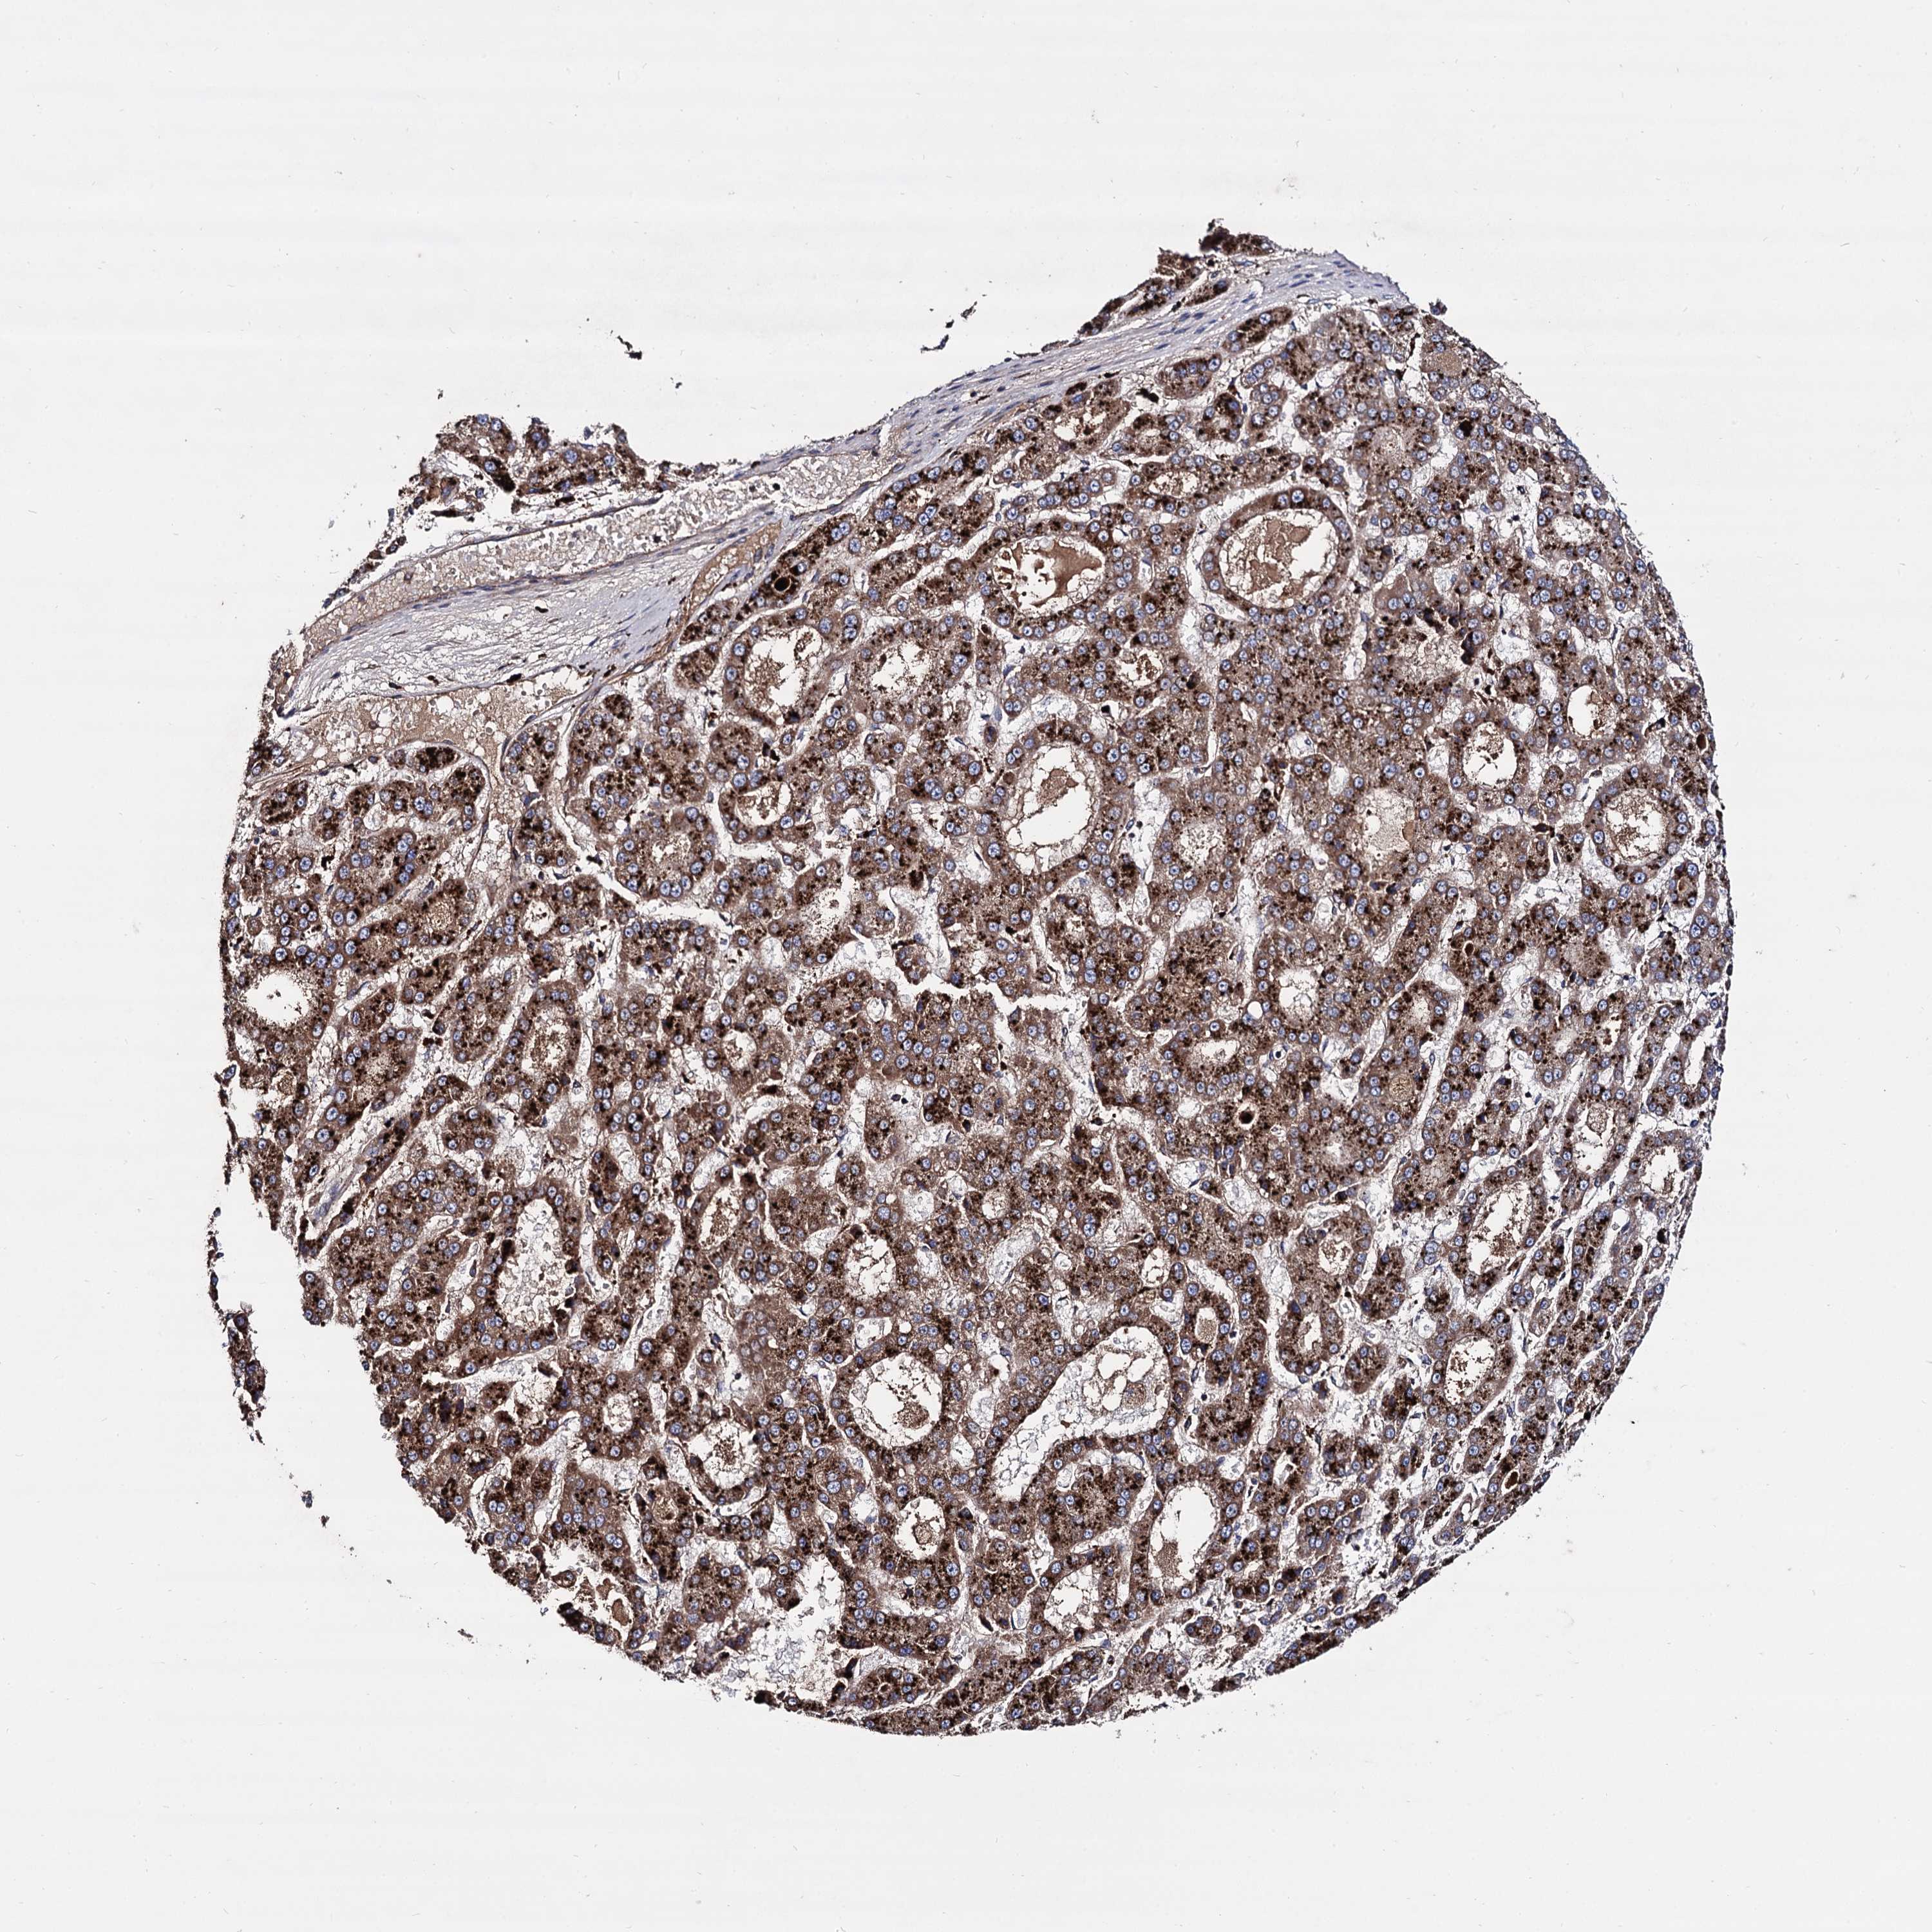

LIVER CANCER - Protein expressioni

A mouse-over function shows sample information and annotation data. Click on an image to view it in a full screen mode. Samples can be filtered based on level of antibody staining by selecting one or several of the following categories: high, medium, low and not detected. The assay and annotation is described here.

Note that samples used for immunohistochemistry by the Human Protein Atlas do not correspond to samples in the TCGA dataset.

Antibody stainingi

Antibody staining in the annotated cell types in the current human tissue is reported as not detected, low, medium, or high, based on conventional immunohistochemistry profiling in selected tissues. This score is based on the combination of the staining intensity and fraction of stained cells.

Each image is clickable and will lead to virtual microscopy that enables deeper exploration of all samples and also displays staining intensity scores, fraction scores and subcellular localization as well as patient and tissue information for each sample.

Antibody HPA040845

Staining

High

Medium

Low

Not detected

Intensity

Strong

Moderate

Weak

Negative

Quantity

>75%

75%-25%

<25%

None

Location

Nuclear

Cytoplasmic/membranous

Cytoplasmic/membranous,nuclear

Cholangiocarcinoma

Carcinoma, Hepatocellular, NOS